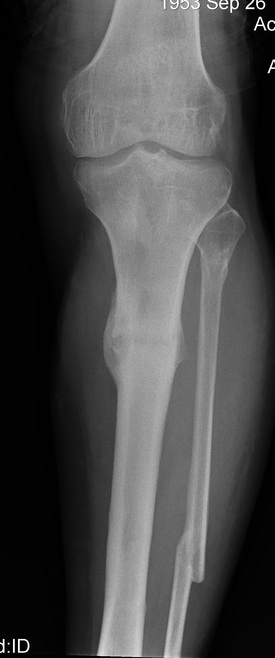

2. С аппаратом и резекцией малоберцовой кости все понятно, но почему вы предполагаете значимое укорочение, требующее транспорта? В моем случае есть признаки формирования нормотрофического (по крайней мере не аваскулярного несращения)- в приложении боковая рентгенограмма.

Качество остеосинтеза (по центрированным снимкам)я расцениваю как удовлетворительное.

1) Некроза нет, кость в области перелома жизнеспособна (представленная рентгенограмма позволяет на это надеяться).

Итак - удалили стержень, воспалительный процесс к тому моменту купирован, наложили кастовую повязку и в течение 3 месяцев на контрольных рентгенограммах - признаки консолидации. Уже в сентябре, т.е черз 5 месяцев после нагноения пациент вернувшиь с подвождной охоты привез здорового сазана - основная жалоба - ноги побаливают после длительного лпаваня в ластах. Прилагаю снимки через год после удаления стержня. Вот такая, на этот раз счастливая казуистика.